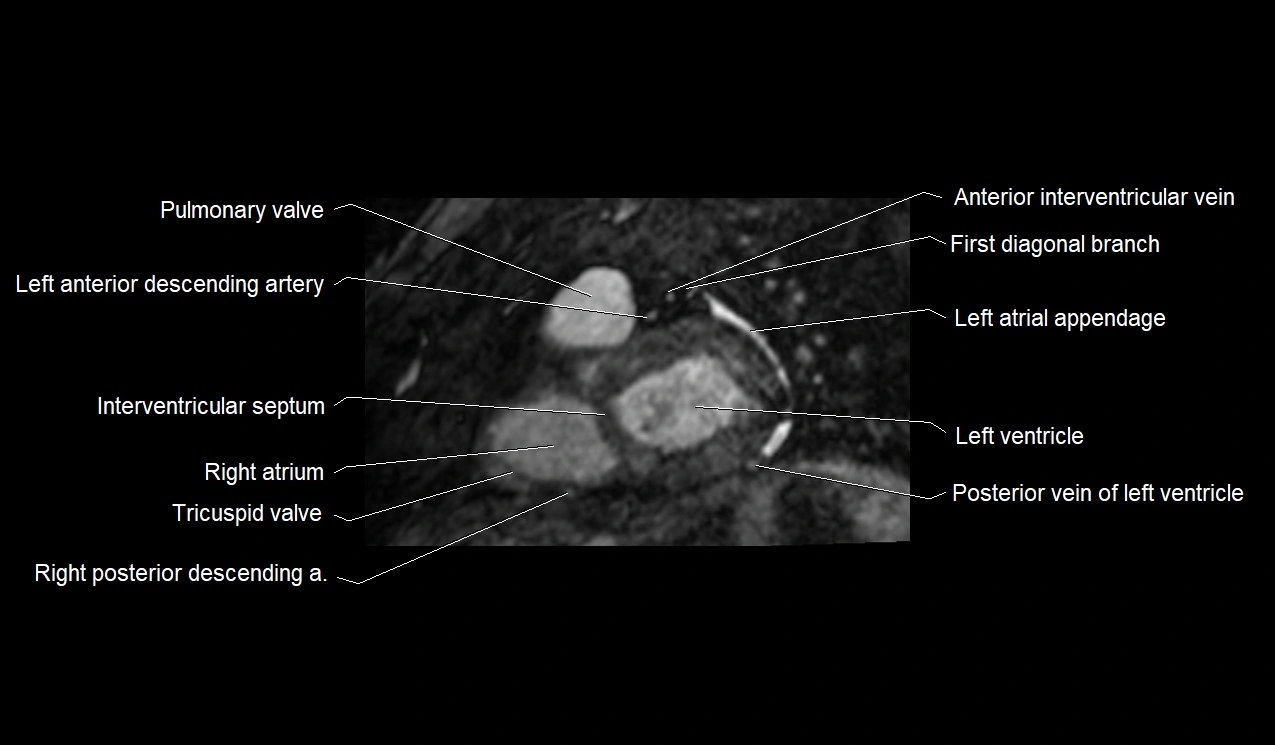

MRI image